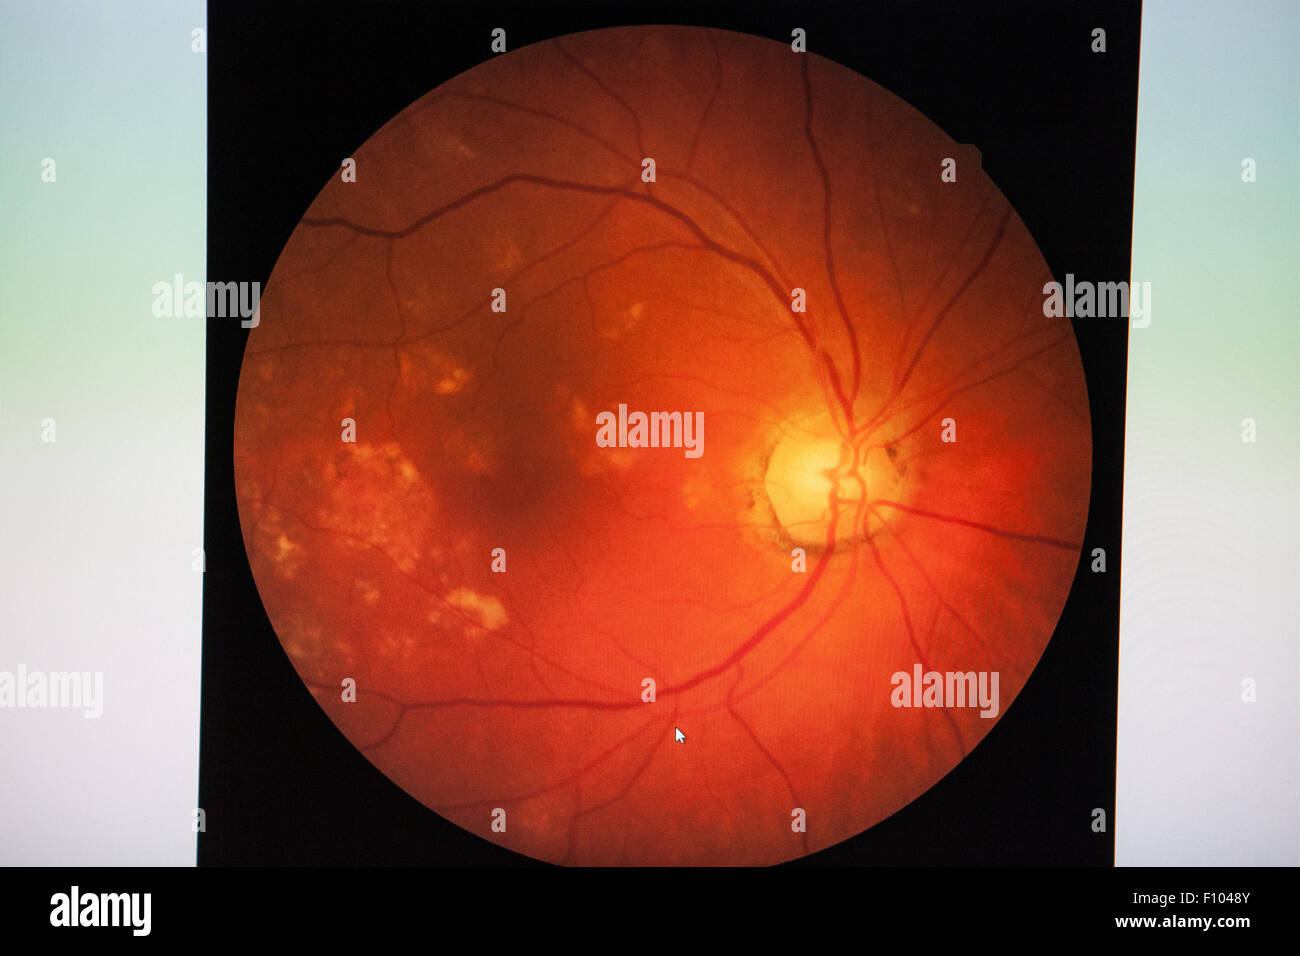

FUNDUS OCULI Stock Photohttps://www.alamy.com/image-license-details/?v=1https://www.alamy.com/stock-photo-fundus-oculi-86669883.html

FUNDUS OCULI Stock Photohttps://www.alamy.com/image-license-details/?v=1https://www.alamy.com/stock-photo-fundus-oculi-86669883.htmlRMF1048Y–FUNDUS OCULI